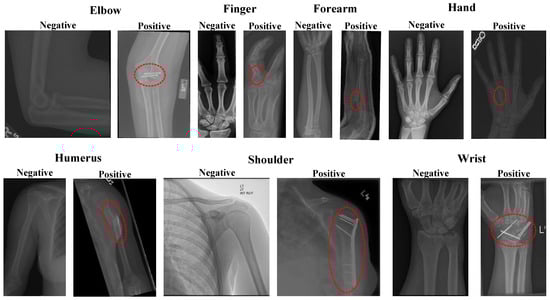

2.1. Dataset

- Rajpurkar, P.; Irvin, J.; Bagul, A.; Ding, D.; Duan, T.; Mehta, H.; Yang, B.; Zhu, K.; Laird, D.; Ball, R.L. Mura: Large dataset for abnormality detection in musculoskeletal radiographs. arXiv 2017, arXiv:1712.06957. [Google Scholar]

| Classes | Accuracy (%) | Specificity (%) | F1-Score (%) | Recall (%) | Precision (%) | |

|---|---|---|---|---|---|---|

| Elbow | Negative | 92.04 | 86.18 | 93.45 | 96.10 | 90.94 |

| Positive | 96.10 | 89.86 | 86.18 | 93.87 | ||

| Finger | Negative | 91.19 | 87.45 | 92.88 | 93.53 | 92.24 |

| Positive | 93.53 | 88.44 | 87.45 | 89.45 | ||

| Forearm | Negative | 92.11 | 84.57 | 93.97 | 96.39 | 91.67 |

| Positive | 96.39 | 88.59 | 84.57 | 93.01 | ||

| Hand | Negative | 91.34 | 76.28 | 94.25 | 96.85 | 91.78 |

| Positive | 96.85 | 82.51 | 76.28 | 89.84 | ||

| Humerus | Negative | 91.35 | 88.15 | 92.02 | 94.21 | 89.93 |

| Positive | 94.21 | 90.57 | 88.15 | 93.12 | ||

| Shoulder | Negative | 89.49 | 87.81 | 89.70 | 91.14 | 88.31 |

| Positive | 91.14 | 89.26 | 87.81 | 90.75 | ||

| Wrist | Negative | 92.63 | 88.74 | 93.86 | 95.32 | 92.45 |

| Positive | 95.32 | 90.78 | 88.74 | 92.91 | ||